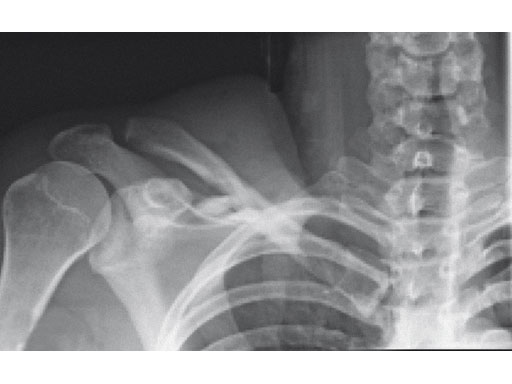

Fig 3ab X-rays taken 3 months postoperatively.

Case provided by Harry A Hoyen III, Cleveland, USA